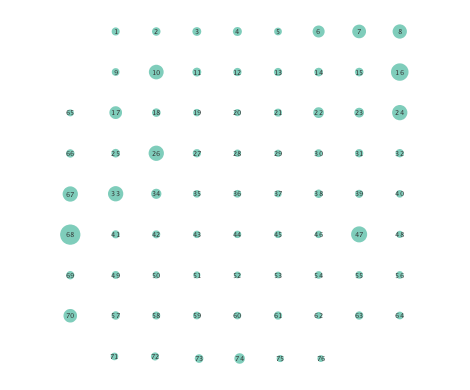

Figure 2 depicts networks inferred from different algorithms for both preictal and ictal intervals of the time series. The figure illustrates results obtained by the linear SVARM, and the K-SVARM approach with and without kernel selection. Each node in the network is representative of an electrode, and it is depicted as a circle, while the node arrangement is forced to remain consistent across the four visual representations. A cursory inspection of the visual maps reveals significant variations in connectivity patterns between ictal and preictal intervals for both models. Specifically, networks inferred via the K-SVARMs, reveal a global decrease in the number of links emanating from each node, while those inferred via the linear model depict increases and decreases in links connected to different nodes. Interestingly, the K-SVARM with kernel selection recovered most of the edges inferred by the linear and the K-SVARM using a polynomial kernel, which implies that both linear and nonlinear interactions may exist in brain networks. Clearly, one is unlikely to gain much insight only by visual inspection of the network topologies. To further analyze differences between inferred networks from both models, and to assess the potential benefits gained by adopting the novel scheme, several network topology metrics are computed and compared in the next subsection.

First, in- and out-degree was computed for nodes in each of the inferred networks. Note that the in-degree of a node counts its number of incoming edges, while the out-degree counts the number of out-going edges. The total degree per node sums the in- and out-degrees, and is indicative of how well-connected a given node is. Figure 3 depicts nodes in the network and their total degrees encoded by the radii of circles associated with the nodes. As expected from the previous subsection, Figures 3 (a) and (b) demonstrate that the linear SVARM yields both increases and deceases in the inferred node degree. On the other hand, the nonlinear SVARM leads to a more spatially consistent observation with most nodes exhibiting a smaller degree after the onset of a seizure (see Figures 3 (c) and (d)), which may imply that causal dependencies thin out between regions of the brain once a seizure starts.